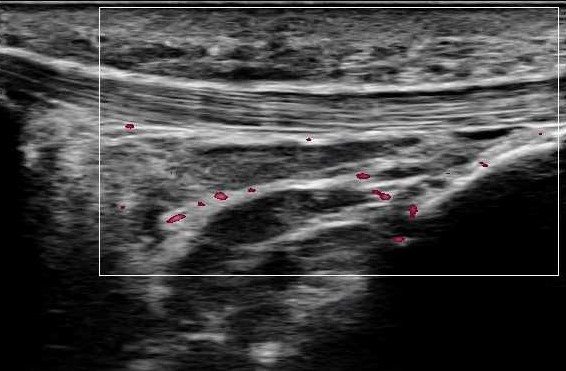

レントゲン:明らかな損傷なし超音波:膝蓋腱・膝蓋下脂肪体 炎症反応+

膝蓋腱と脂肪体に炎症反応を認めた。膝を伸ばす可動域が非常に柔らかいため、伸びすぎないよう自身でコントロールできるように膝周囲の筋力強化を実施した。